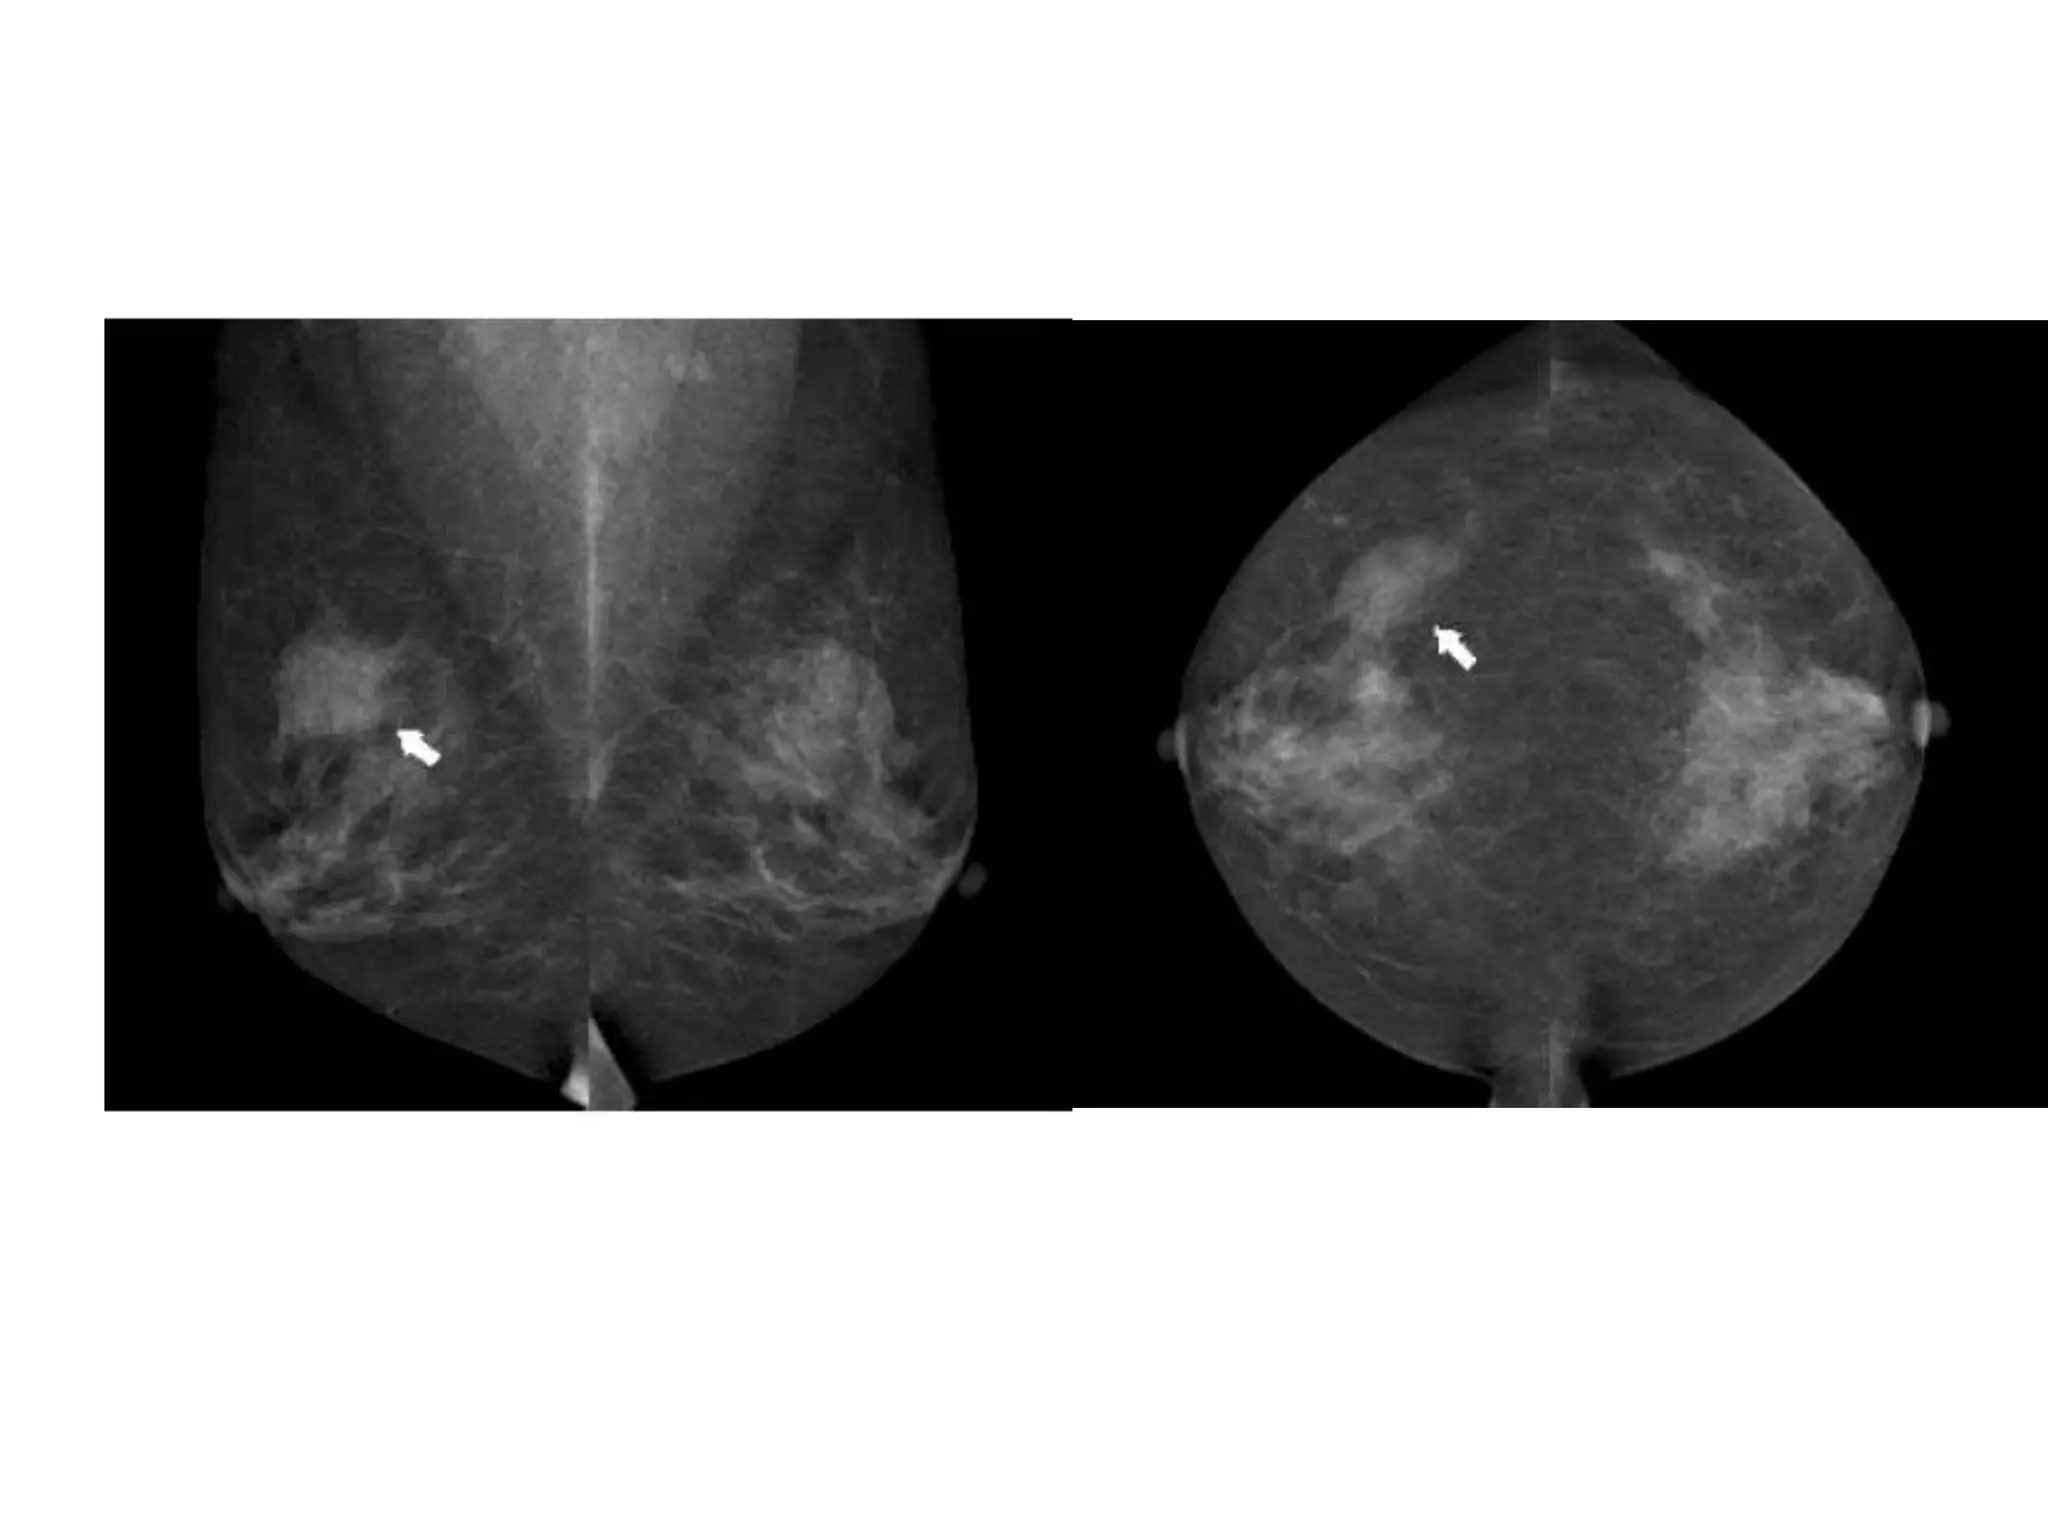

• #52 Figure 3: Global asymmetry seen in (a) schematic, (b) MLO views, and (c) CCviews. A much greater volume of breast tissue is seen over a substantial portion of theleft breast relative to the corresponding region in the right breast, but there is noassociated mass, suspicious calcifications, or architectural distortion.

• #54 Figure 4: Focal asymmetry seen in (a) schematic, (b) MLO views, and (c) CC views.A focal asymmetry with a similar shape (arrows), not fitting the criteria of a mass, isseen on two standard views.Developing AsymmetryThis is a focal asymmetry that is new, larger, or denser at current examination thanat previous examinations (Fig 5). To identify such a lesion, comparison with previousmammograms is critical. It raises a reasonable degree of suspicion and requiresadditional evaluation in the absence of a history of hormonal therapy, surgery, trauma,or infection at the site. It is an uncommon mammographic finding, reported in less than1% of examinations, but the likelihood of malignancy ranges from 13% to 27% (Fig 6)(4).5a.10

FOCAL ASYMMETRY

• Is seen in both the views.

• Involves a less than one quadrant of breast.

• It can be due to normal variations or some lesion.

DEVELOPING ASYMMETRY

• This is a focal asymmetry that is new, larger, or

denser at current examination than at previous

examinations.